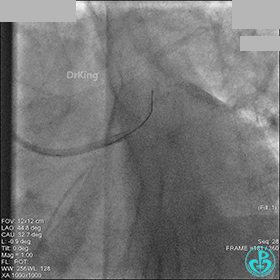

AL 1.0指引导管到位,简单短时尝试导丝不能顺利通过前降支或回旋支病变。改变策略处理右冠脉病变,计划植入2枚支架。AL指引导管到位,Sion blue导丝到达右冠脉远端。导丝通过后1.5mm及2.5mm球囊14~16atm充分扩张中段病变。

右冠脉中段充分扩张后欲植入3.5×38mm支架时,支架难以通过中远段扭曲处,且指引导管、导丝弹出飞扬。反复尝试导丝重新到达右冠脉远端时通过不顺利,局部造影剂滞留,远端血流接近3级。